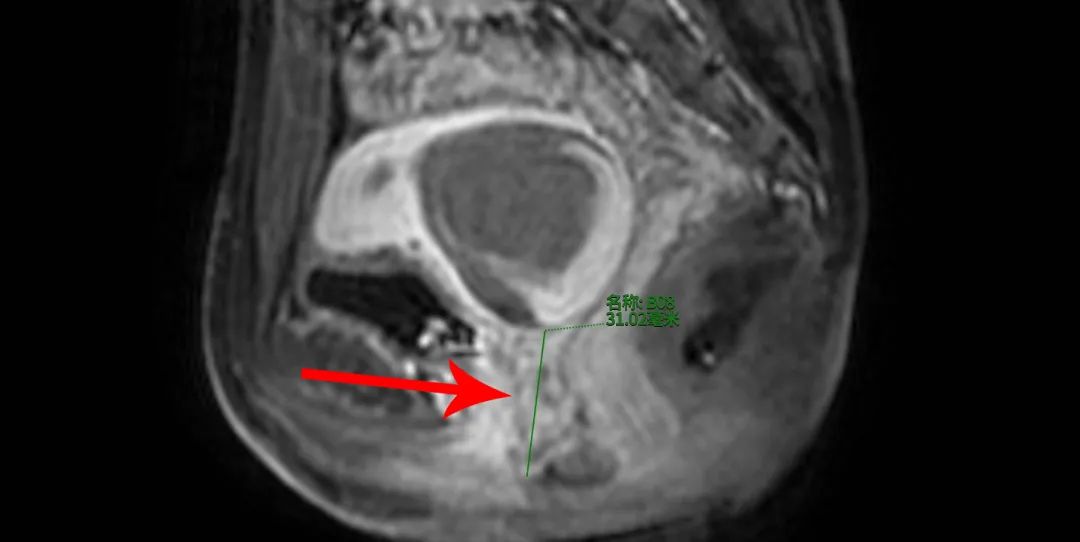

入院后,妇科超声检查提示:宫颈下方有液性暗区,考虑阴道下段闭锁。随后进一步完善了相关检查,经盆腔磁共振检查,结果显示小雨阴道下段空虚,范围约3.1厘米,宫腔积血,诊断为“I型阴道闭锁”。子宫里的经血无法经过阴道排出体外,便聚集在阴道上段和子宫内,像一个鼓鼓囊囊的“气球”,导致月经路不通,这也是她为什么产生剧烈下腹痛的原因,需要手术治疗。

阴道下段闭锁长度31mm